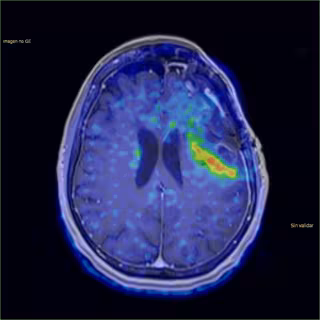

Imagen tumor cerebral